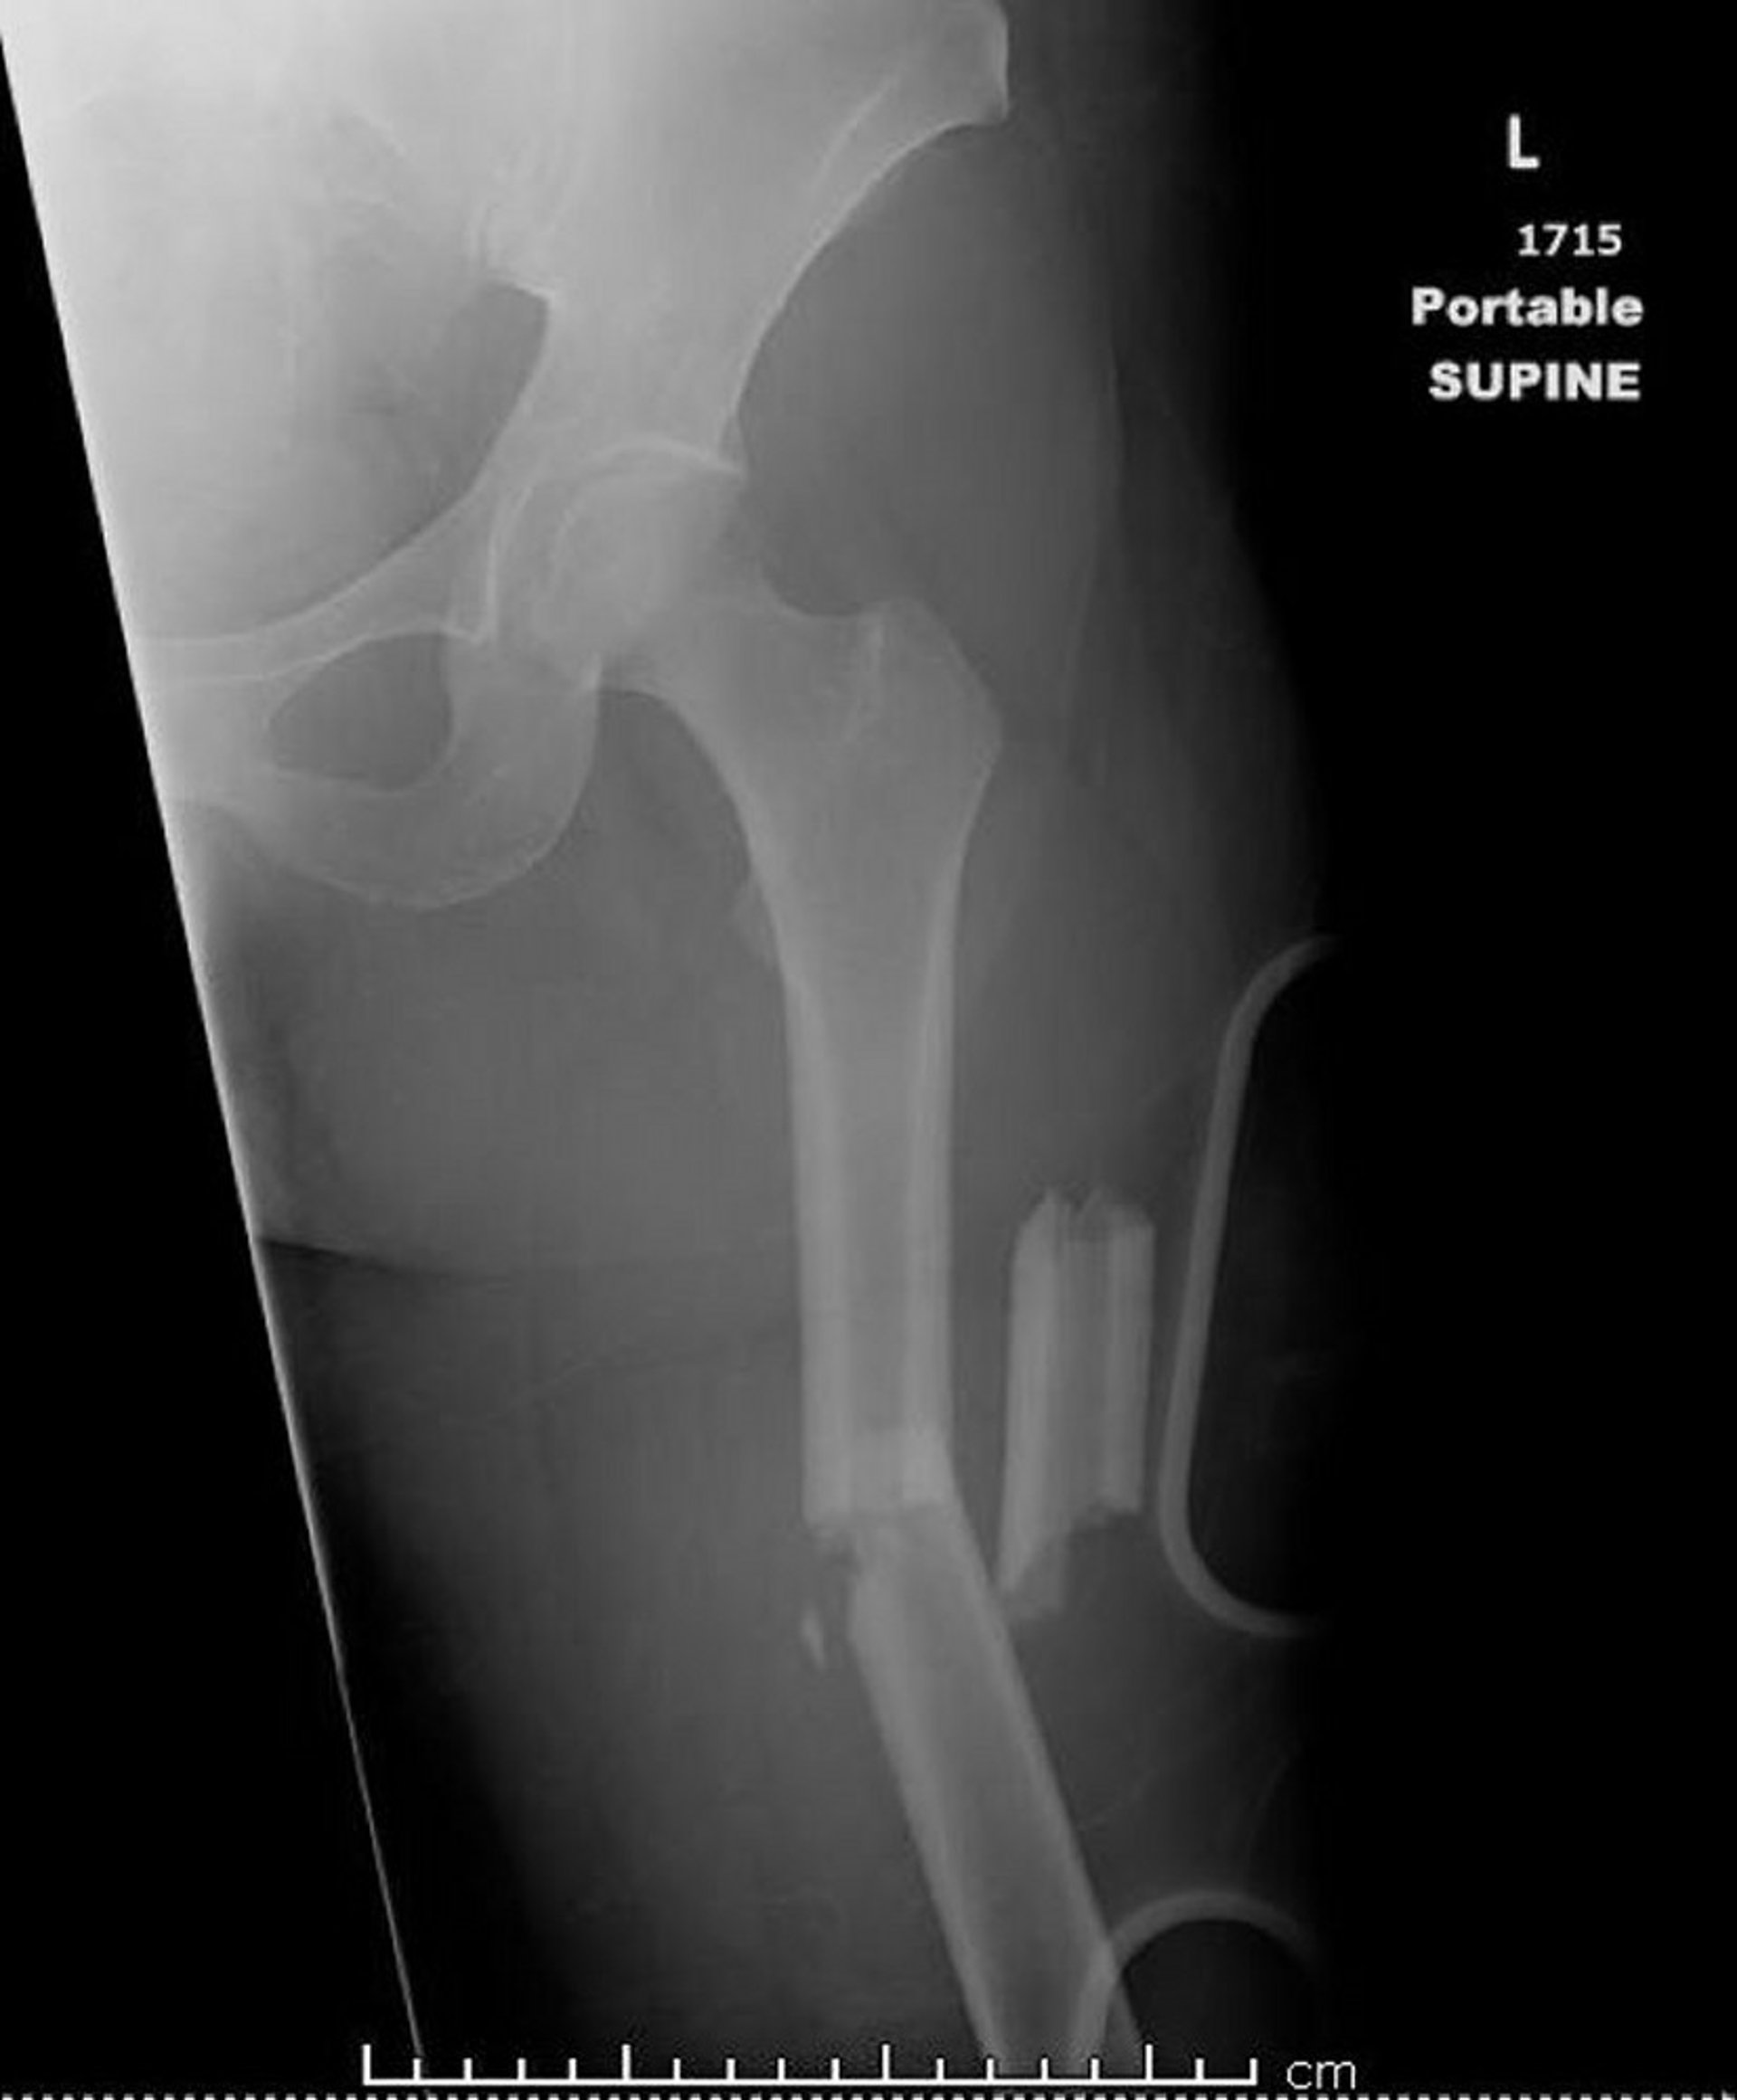

Auf diesem Bild ist ein Oberschenkelknochen (Femur) zu sehen, der an mehr als zwei Stellen gebrochen ist (zertrümmert).

Bild mit freundlicher Genehmigung von Dr. med. Danielle Campagne.